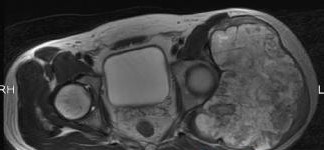

3.CT检查:在中央型与周缘型软骨肉瘤中均有用途,可以了解肿瘤在骨内及软组织中的范围。在周缘型软骨肉瘤的帽盖的厚度,可以帮助分析原来存在的骨软骨瘤有无恶变。

3.辅助检查:软骨肉瘤X线表现为一密度减低的阴影,病灶中有斑点状或块状钙化点。放射性核素扫描可用于检查中央型及周缘型软骨肉瘤。CT检查在中央型与周缘型软骨肉瘤中均有用途,可以了解肿瘤在骨内及软组织中的范围。在周缘型软骨肉瘤的帽盖的厚度,可以帮助分析原来存在的骨软骨瘤有无恶变。病理检查:是软骨肉瘤诊断的金标准。